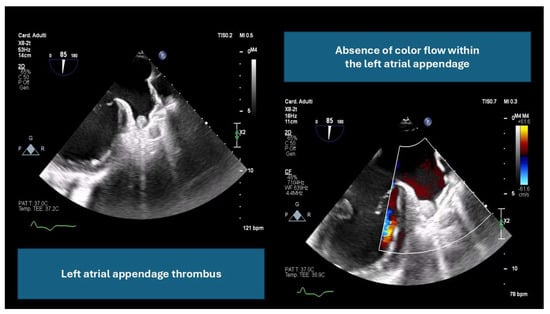

- By ruling out LAA thrombus, which can increase the risk of embolic events (an example is provided in Figure 1).

- By providing detailed anatomical assessment, including LAA dimensions, peak emptying velocity, and surrounding structures.